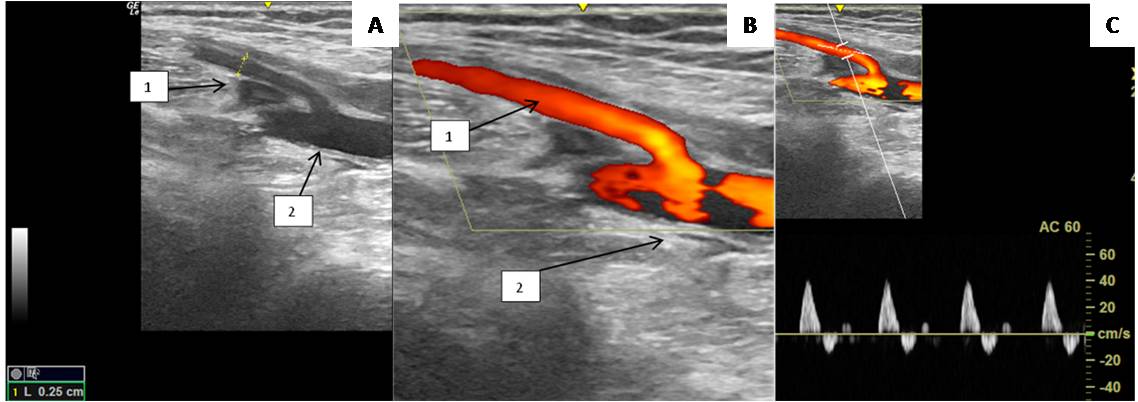

The sural veins were visualized in all patients, usually two on the medial and lateral surfaces, forming a single trunk before joining the PV and located at the sides of the sural arteries. It is important to note that the sural artery is a fairly large vessel, 2.8 ± 0.3 mm in diameter, which suggests its significant role in the development of collateral circulation in patients with peripheral atherosclerosis (Figure 6).

Fig. 6. Duplex scan of the sural artery; (A) B-mode; (B) Color Doppler mapping mode; (C) Spectral Dopplerography mode.

Notes: (1) Popliteal artery; (2) Sural artery.